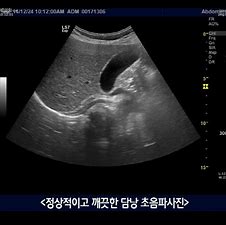

복부초음파는 담낭용종을 진단하는 데 가장 유용한 검사입니다.

담낭용종은 자각증상이 거의 없어서,

건강검진을 받던 중 복부초음파에서 우연히 발견하는 경우가 많습니다.